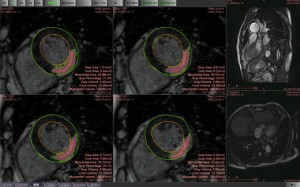

○MR遅延造影解析(図4)